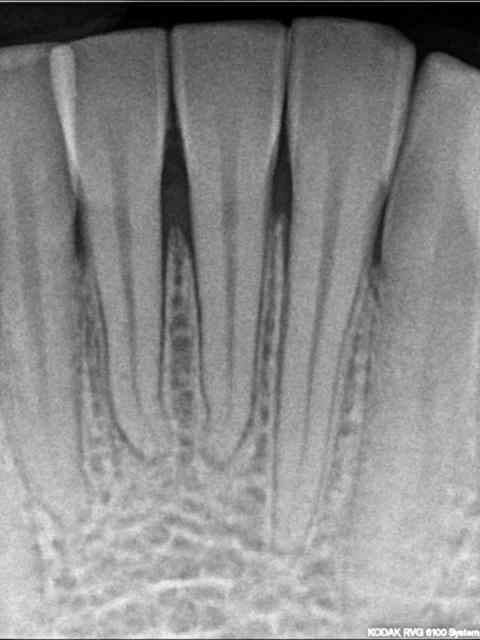

Patient de 21 ans, bon état bucco-dentaire, bonne hygiène, fumeur 1 paquet/jour, pharyngite il y a une semaine, petits ganglions sub-mandib à gauche, lésions d'aspect "bouton de fièvre" sur les lèvres, fièvre moderée, RAS au niveau général.

Je le reçois en urgence pour "douleurs très fortes aux gencives depuis 2 jours".

Le tableau clinique m'a semblé très typique d'une GUN : gingivite généralisée en haut et en bas, sommets des papilles recouverts d'un enduit grisâtre au niveau des blocs antérieurs, douleurs importantes, halitose.

Un point me semble un peu étrange : les 4 incisives du bas sont mobiles, et cette mobilité est vraiment importante pour 31-41. Pourtant la radio ne révèle pas d'alveolyse significative. Le patient me dit avoir remarqué cette mobilité et qu'elle n'existait pas avant.

Est-ce une parodontite ulcéro-nécrotique ? J'ai fait des bite-wing des deux côtés, je ne vois rien de particulier.